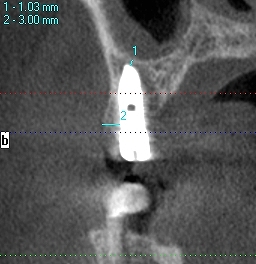

CTにより解剖学的形態を避け、安全に顎骨内にインプラントを埋入することが大切です。 CTが無いとインプラントはリスクが高いです

CTにより解剖学的形態を避け、安全に顎骨内にインプラントを埋入することが大切です。 CTが無いとインプラントはリスクが高いです

将来的に周囲の歯が無くなっても安定した位置への埋入

になっているかと思います